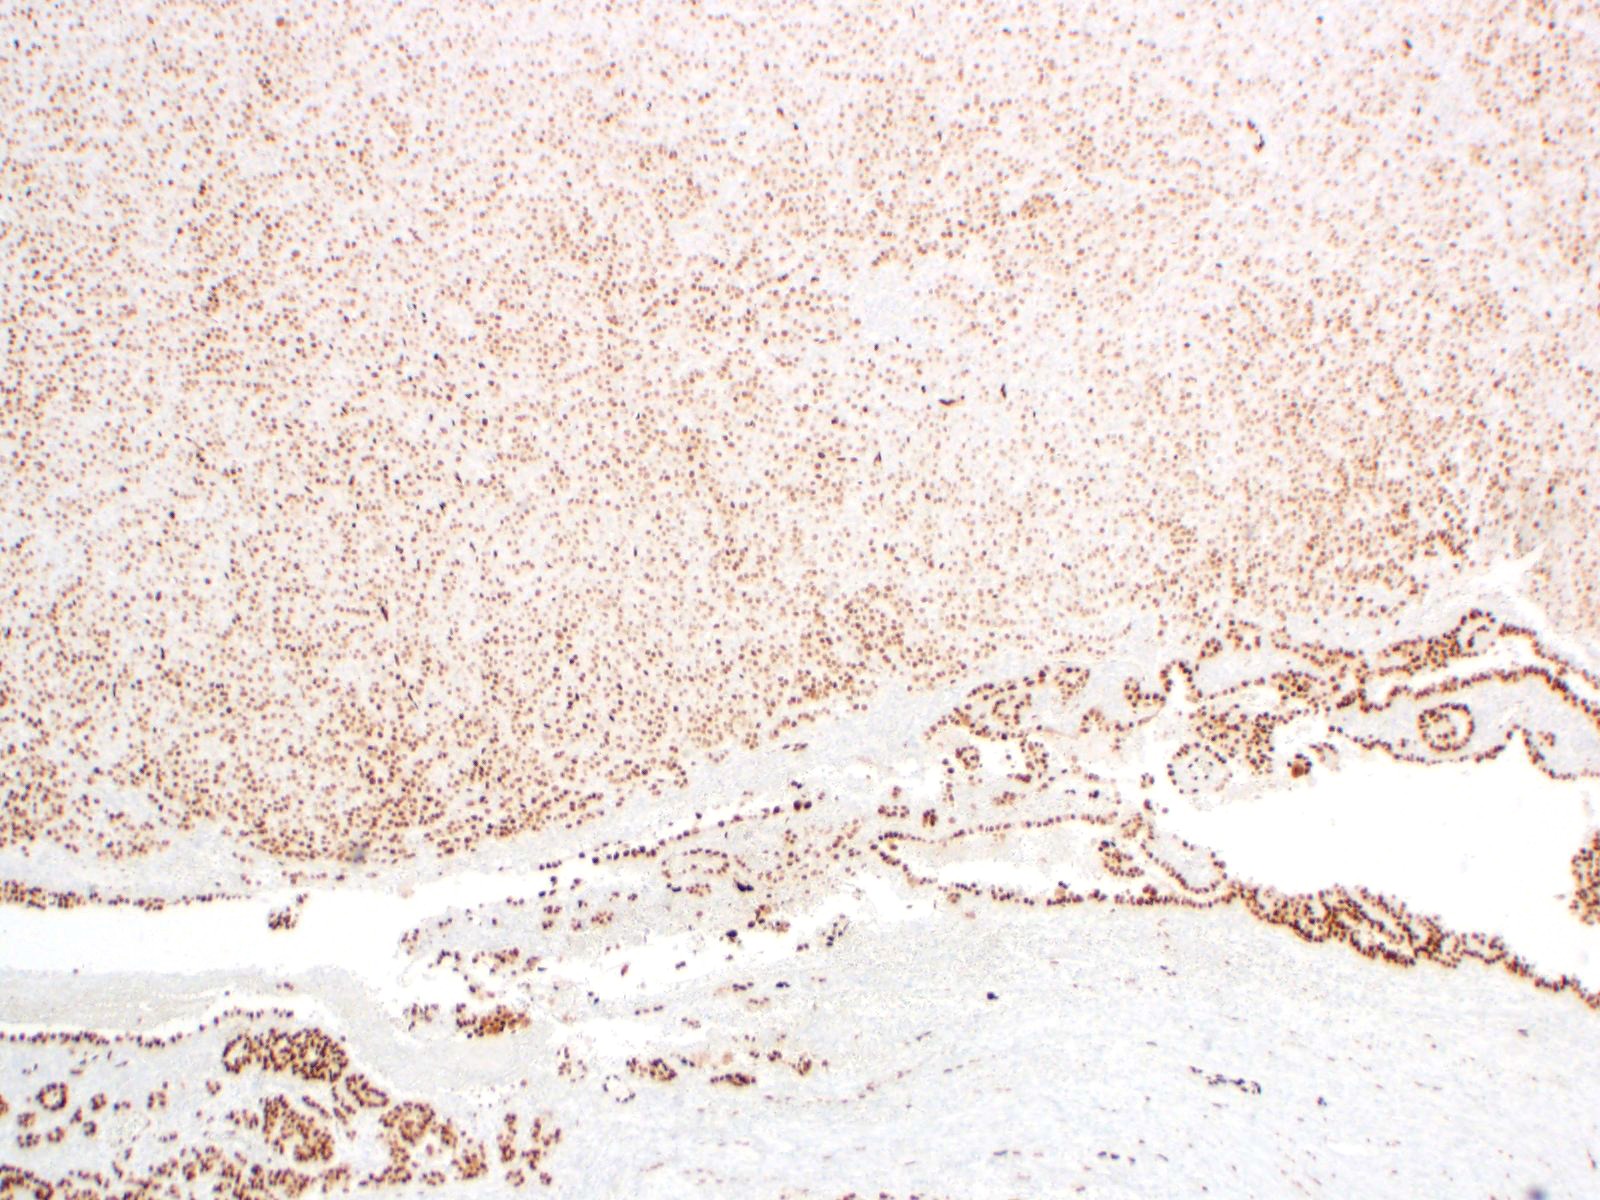

| 2SC |

S-(2-succino)-cysteine |

Rabbit polyclonal (Cambridge Research Biochemicals)

Hereditary leiomyomatosis and renal cell carcinoma (HLRCC) syndrome-associated RCC and leiomyoma

Most renal tumors and leiomyomas not associated with HLRCC

Staining Pattern

Cytoplasmic and nuclear

| Non-HLRCC-associated RCC |